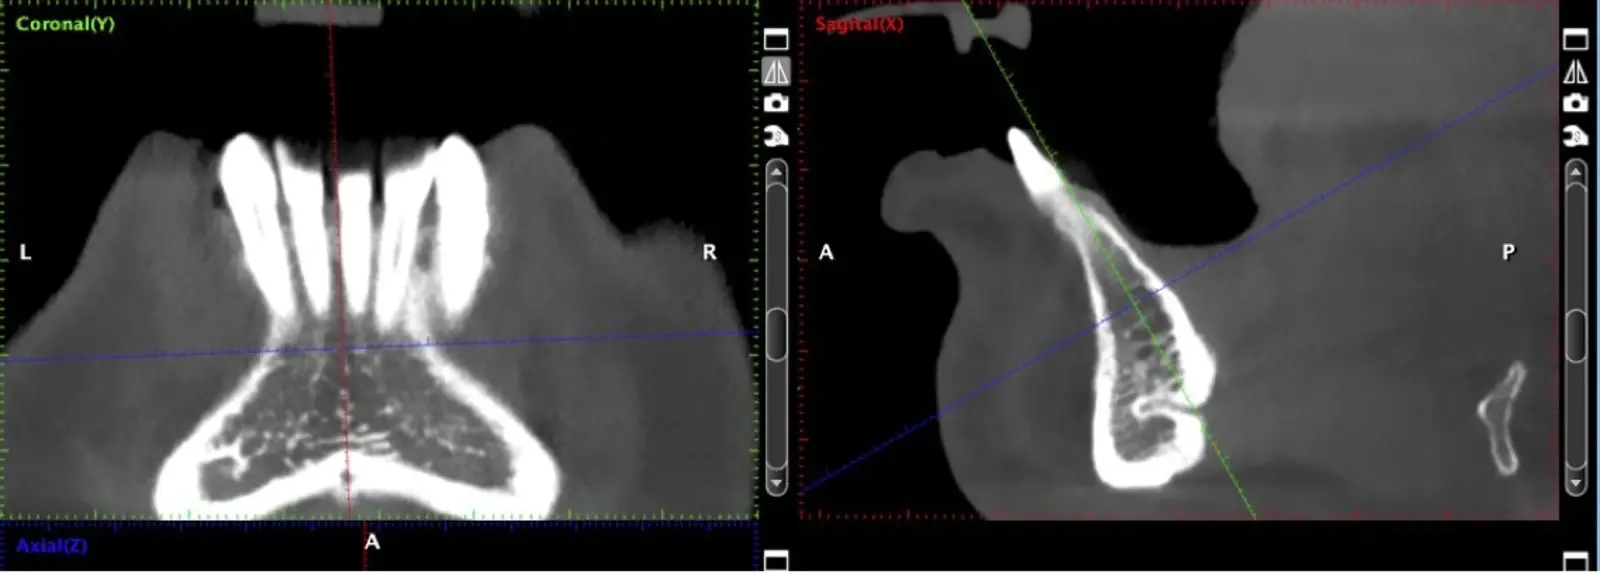

En los últimos años, la rehabilitación de pacientes edéntulos mediante implantes osteointegrados se ha convertido en una modalidad de tratamiento predecible siempre que exista un volumen de hueso residual adecuado. Se ha demostrado que para lograr resultados confiables el implante dental insertado debe mantener una pared ósea vestibular de al menos 1 mm de espesor.1 En pacientes clase IV, según la clasificación de Cawood & Howell2, la cresta alveolar puede tener un ancho insuficiente con una morfología denominada “filo de cuchillo”, escenario que puede comprometer la colocación de implantes dentales. Es en esas situaciones clínicas que se hace necesario mejorar las condiciones utilizando alternativas como reconstrucciones con injertos óseos.3-6

El hueso autógeno, considerado como el “gold stándard” para la regeneración ósea, no produce reacciones inmunológicas y contiene componentes osteogénicos, osteoinductores y osteoconductores.7,8 Suele obtenerse en bloques y las zonas dadoras intraorales de elección son la sínfisis mentoniana y la rama mandibular.9

La literatura menciona varias complicaciones relacionadas con la extracción de injertos óseos, la mayoría de ellas asociadas con el corte y la manipulación de zonas próximas a estructuras de riesgo; entre las más comunes, las lesiones nerviosas con consecuente adormecimiento, molestias postoperatorias (abertura bucal limitada, sangrado, hinchazón y dolor) y problemas estéticos (cambios en el contorno del área donadora o recesión de tejidos blandos).10 Aunque los injertos de rama pueden presentar menos molestias postoperatorias, tienen un acceso quirúrgico limitado debido a la apertura bucal y el peligro potencial de lesionar el paquete vásculo-nervioso cercano.11

El uso de vibraciones ultrasónicas se introdujo por primera vez hace dos décadas para superar las limitaciones de la instrumentación tradicional.12,13 Altiparmak y cols.14 reportaron en su estudio que la cirugía piezoeléctrica redujo significativamente la incidencia de alteraciones sensoriales tanto de la piel como de la mucosa oral, y redujo también el daño pulpar en los dientes adyacentes, sobre todo en los injertos sinfisiarios.

La osteotomía con insertos de piezoeléctrico nos permite un corte más definido con menor pérdida de hueso residual, ya que los insertos son extremadamente finos.